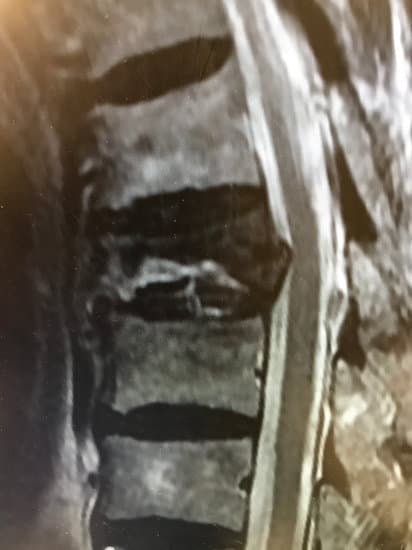

4. 진단 방법

📌 MRI는 골절이 '최근 발생했는지' 판단할 수 있어 치료 계획에 중요합니다.